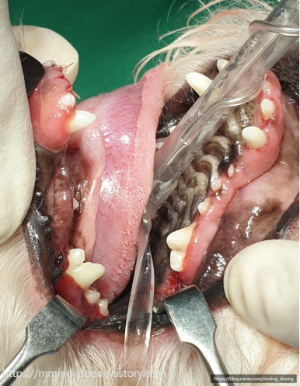

손쓸 수 없는 치아는 어쩔 수 없이 발치했고

치료가 가능한 이빨은 우선 최대한

치주염치료로 살려보자고 하셨다ㅠㅠ

우선적으로 더 안좋은것들부터 순서를 나눴다

다만..치료할 치아가 너어무 많아서..ㅎ

한 번에 모두 진행하기는 무리가 있었고